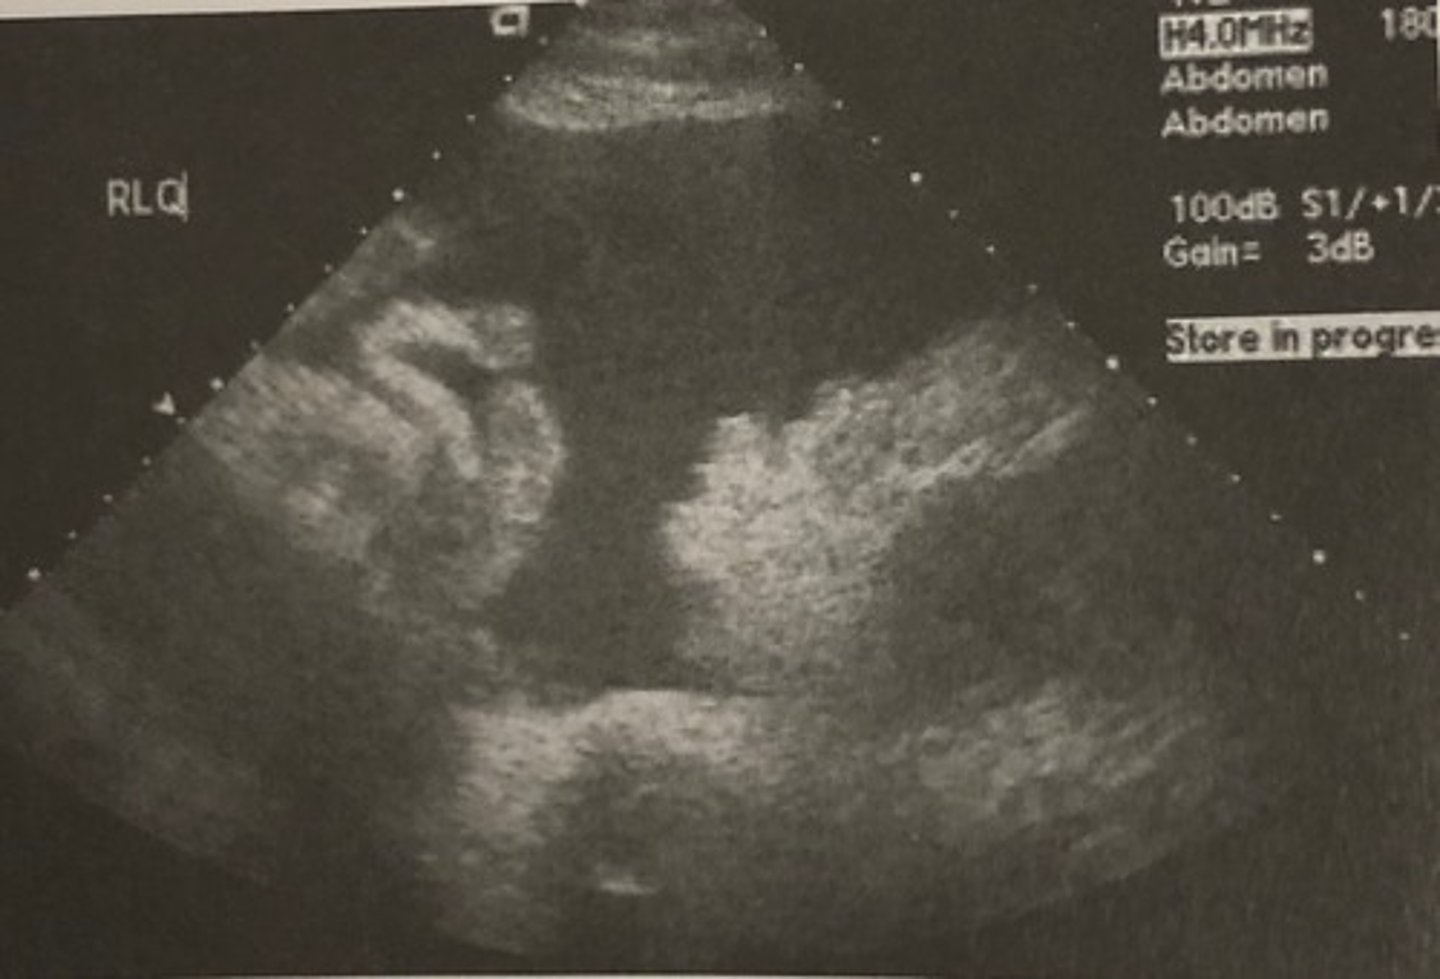

C. Pelvic ascites.

637. This longitudinal sonogram through the right lower quadrant of the patient described in question 636 suggests:

A. Ruptured appendix

B. Endometriosis

C. Pelvic ascites

D. Ruptured ectopic pregnancy

E. Pelvic inflammatory disease